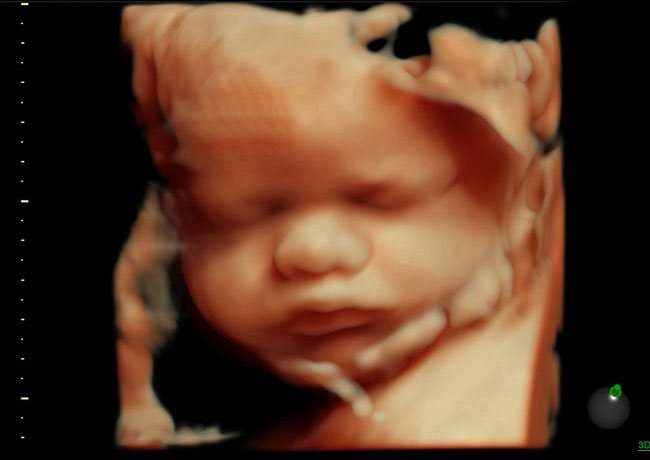

3D УЗИ — это метод, дающий трёхмерное изображение ребёнка в полости матки. С его помощью, в отличие от предыдущего метода, можно увидеть рельеф кожи малыша, оценить формирование его сердца, головного мозга, скелета. Здесь также можно сделать снимок и распечатать его.

4D УЗИ — это трёхмерное изображение (то есть 3D), но в режиме реального времени. То есть полости сердца, которые специалист ультразвуковой диагностики по время 3D УЗИ видел только в виде статической картинки, при 4D УЗИ можно уже наблюдать в их рабочем режиме. Точно также и со всеми остальными органами и функциями малыша: врач и родители видят, как он двигается, могут рассмотреть все участки и органы, которые были прикрыты другими частями тела.

Ультразвуковой мониторинг 3D позволяет получить полихромное изображение, отличающееся объемом и четкостью. Врач может изучить все органы плода в 3-х плоскостях. При этом изображение является статичным.

4D УЗИ-видеомониторинг. Эта новейшая технология направлена на изучение плода не просто сразу в нескольких плоскостях, а еще и в движении и в режиме online. Неудивительно, что процедура становится для будущих мам и пап настоящим знакомством с ребенком.